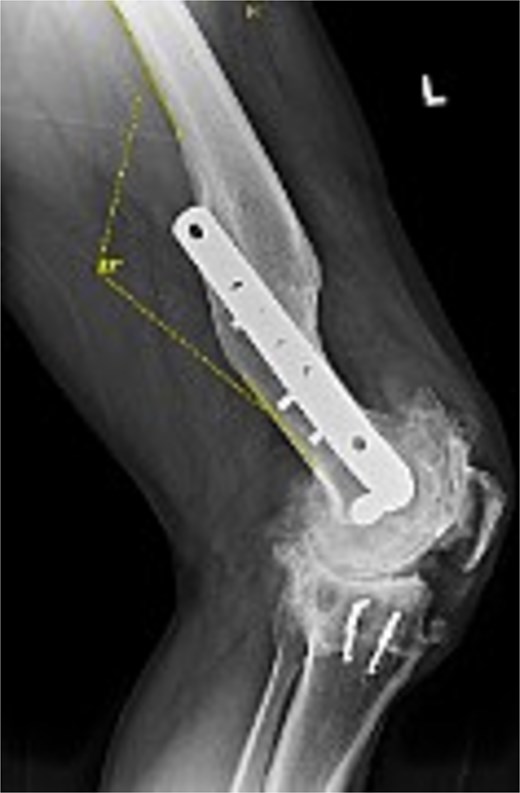

Figures 3 and 4 show a postoperative lateral and AP radiograph of the left knee. The patient was able to fully extend his knee after surgery and instructed to weight bear as tolerated until his two-week follow-up. Patient-reported outcome measures were completed at 2 year follow up (Table 1) with no reported complaints or issues at that time.

Postoperative lateral radiograph of the left knee 1 year after robotic-assisted TKA with hardware retention. The new femoral and tibial components are in place. The retained femoral plate and screws sit flush against the lateral cortex.